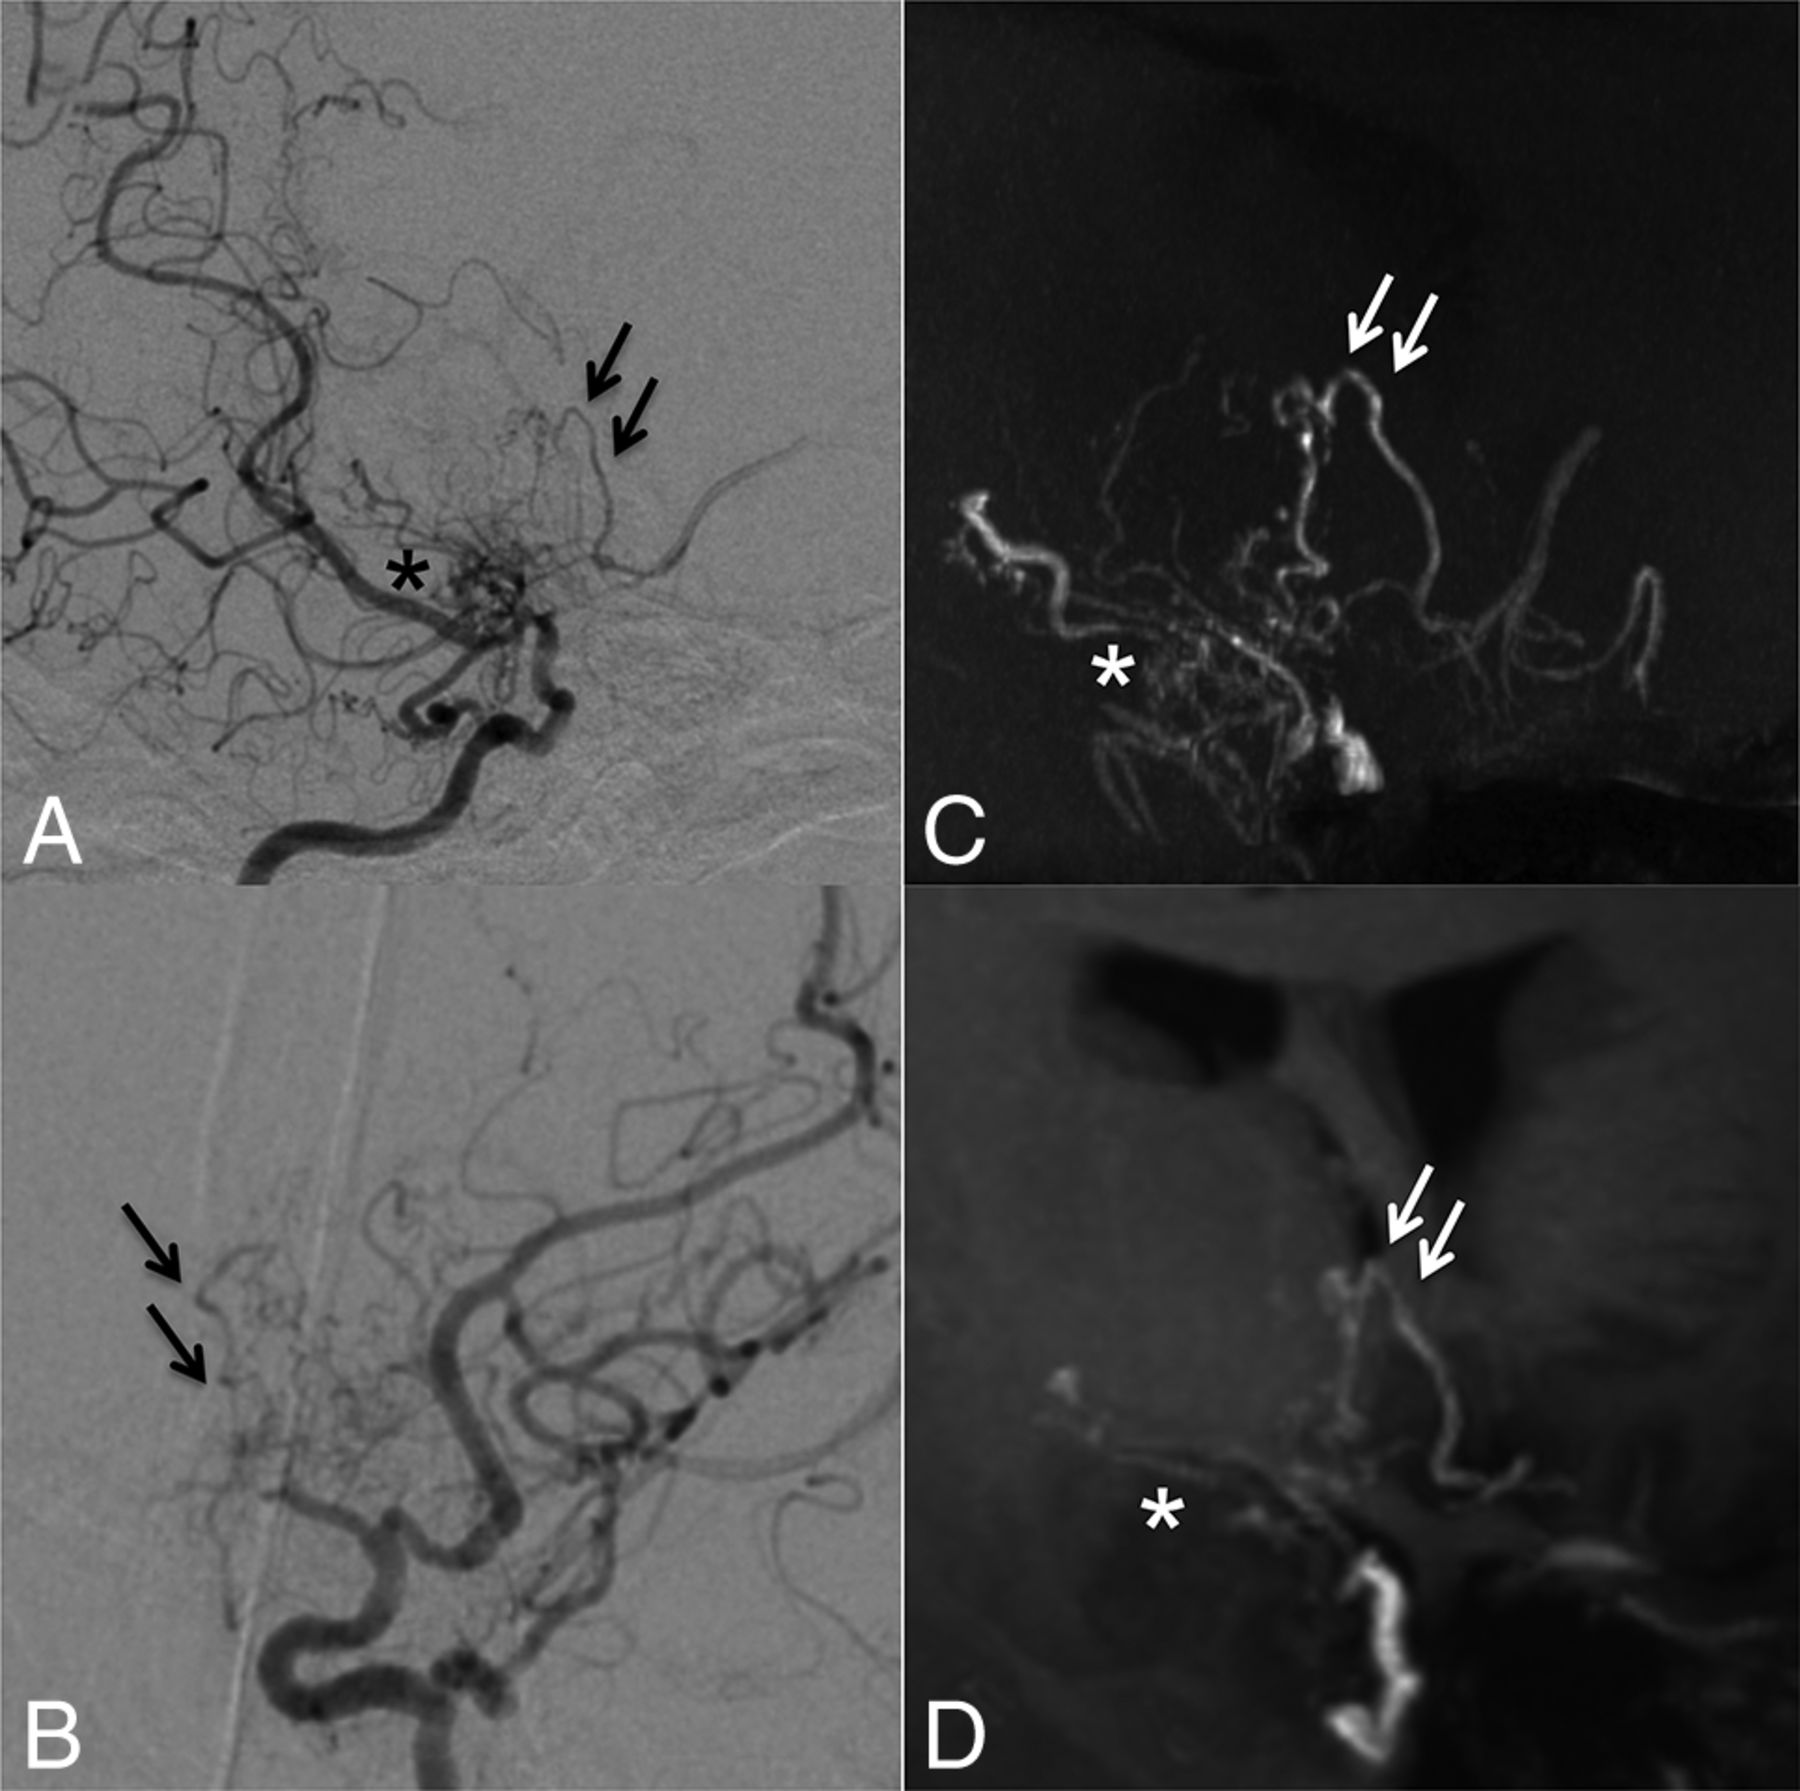

Regarding DSA as a clinical standard, 96 of 100 (96%) collateral networks were delineated in TOF-MRA, and 71 of 100 (71%), in MPRAGE. Figure 6 shows an example of an anastomosis delineated by DSA, but not by TOF-MRA or MPRAGE. Conversely, 9 anastomoses were identified by MRA (TOF: n = 9; MPRAGE: n = 3) that were not visible in DSA images. Seven were anastomoses with cortical arteries, and the others were an inner-striatal and a thalamic anastomosis. These DSA false-negative cases were presumably due to contrast washout and limited viewing angles during the DSA examination. Delineation of DSCNs was comparable between TOF-MRA and DSA (P = .25); however, both were better than MPRAGE (P < .001). The morphologic characteristics and detected number of DSCNs as well as the image quality of each imaging technique are summarized in the Table.

Case 10. Selective right vertebral angiography (anteroposterior, A; lateral view, B) shows a tiny, barely visible anastomosis (black arrows) between the posterior thalamostriate artery and a medullary-cortical artery. MIP from TOF-MRA (C) and MIP from MPRAGE (D) do not delineate the anastomosis. The white arrow (C) indicates the supposed anatomic location of the anastomosis.